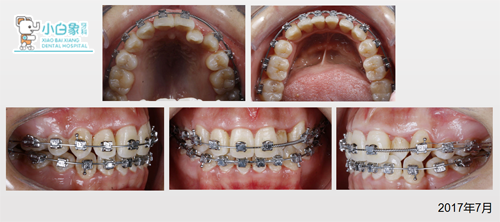

治疗中